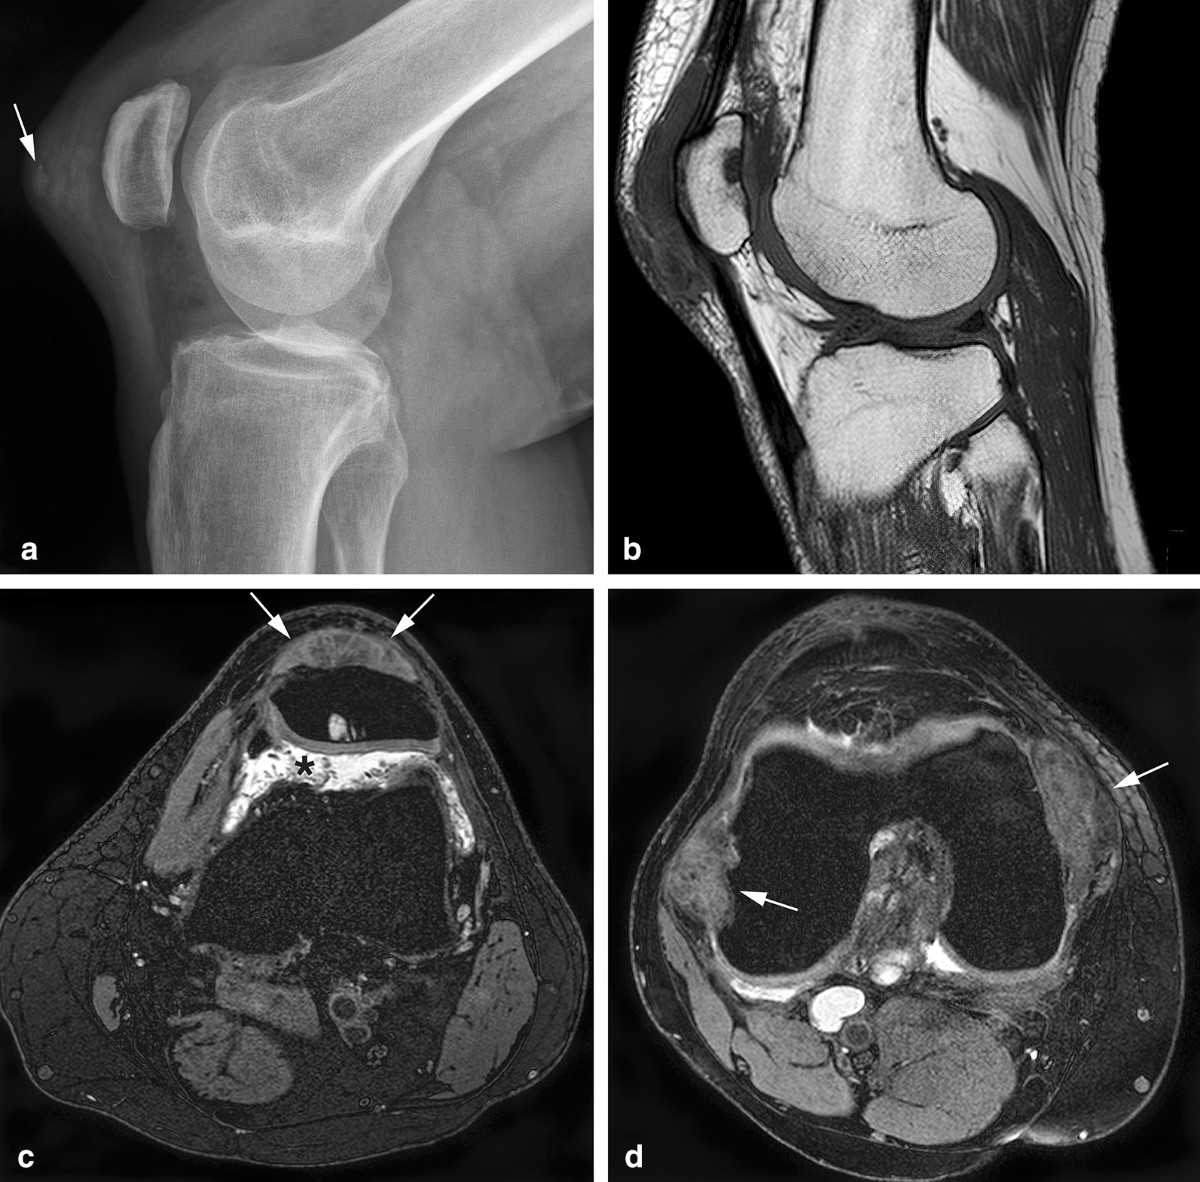

MRI of diffuse-type tenosynovial giant cell tumour in the knee: a guide for diagnosis and treatment response assessment | Insights into Imaging

image size: 1200x1119